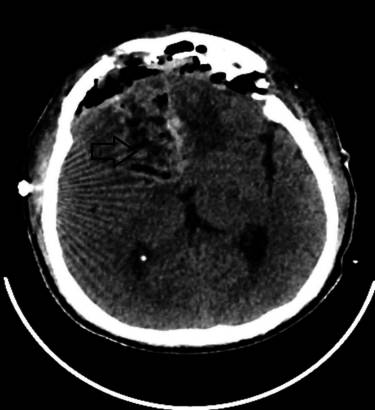

常规术前血液检查在正常范围内,胸部X光检查未发现任何明显异常。大脑的磁共振成像(MRI)发现右额叶存在轴内占位性病变,对左侧胼胝体产生压迫,伴大脑镰下疝。在T1加权图像上,病变表现为等强度(图1),在T2加权图像上表现为高强度(图2),并显示均匀的扩散限制。

图1 术前MRI脑(T1图像);右额叶轴内等强度占位性病变